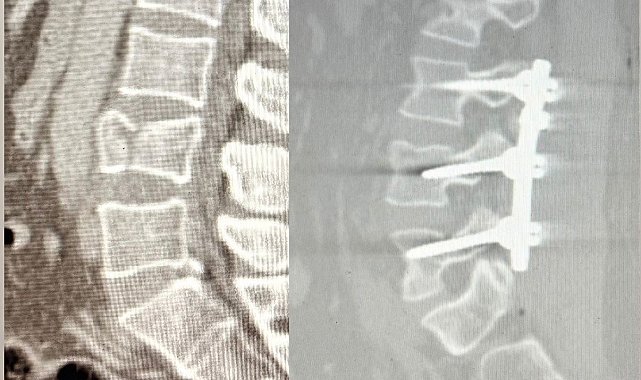

Ağrı'nın Patnos ilçesinde 2,5 metre yüksekten düşen 41 yaşındaki Tekin Maskar, bel bölgesindeki kırık nedeniyle acil servise başvurdu. Yapılan tetkiklerde omurgada çökme kırığı tespit edilmesi üzerine hasta, ortopedi uzmanları Op. Dr. Muhammed Serpi ve Op. Dr. Mustafa İçen tarafından ameliyata alındı.

Ameliyat sırasında bel bölgesindeki omurların sabitlenmesini sağlayan lomber stabilizasyon tekniği kullanıldı. Hastane tarihinde ilk kez gerçekleştirilen bu operasyon sonrası hasta sağlıklı şekilde yürümeye başladı.